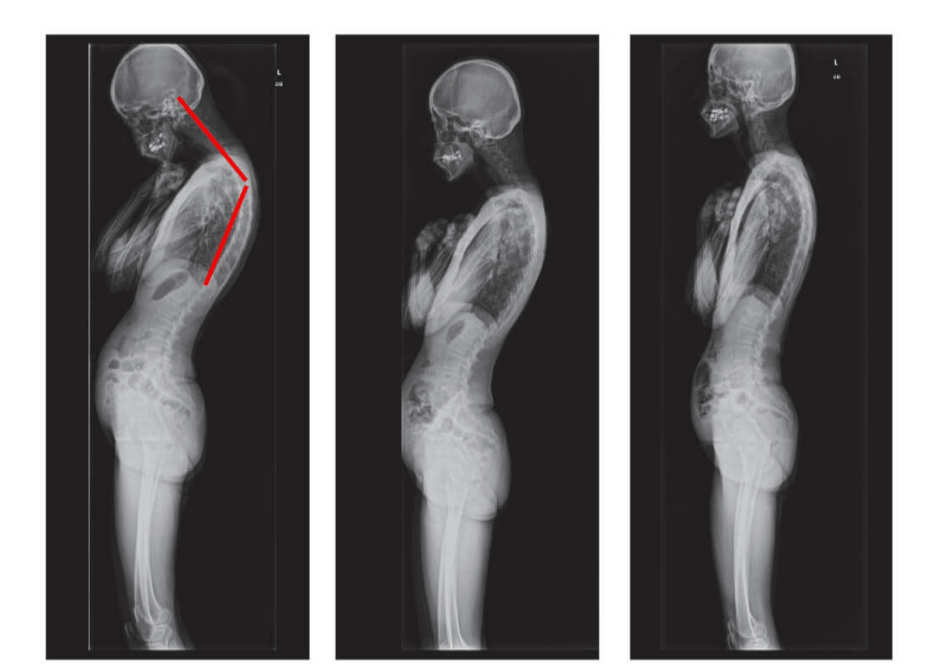

Semua sendi membutuhkan perhatian, tetapi tulang belakang adalah yang paling utama. Jaga kesehatan tulang belakang sebelum perubahan yang tidak dapat diperbaiki terjadi. Inilah yang menanti mereka yang mengabaikan sinyal tubuh: HERNIA, PERGESERAN TULANG BELAKANG, DEFORMASI TULANG BELAKANG, PUNGGUNG BENGKOK, KEHILANGAN TOTAL KEMAMPUAN BERGERAK. Jangan tunggu hingga gerakan paling sederhana pun menjadi siksaan!

Lihat foto-foto ini. Inilah yang terjadi pada mereka yang tidak memperhatikan gejala. Hari ini, mereka adalah orang-orang yang tak berdaya, dan banyak di antara mereka tidak memiliki siapa pun untuk membantu. Apakah Anda menginginkan nasib seperti itu?

Wanita, 52 tahun. Pergeseran parah dan deformasi cakram tulang belakang dengan kompresi saraf serta kerusakan sumsum tulang belakang.

"Punggung bungkuk janda" — deformasi tulang belakang yang menyebabkan nyeri tak tertahankan yang semakin memburuk setiap hari.

Wanita, 62 tahun. Pergeseran tulang belakang yang parah. "Jointlite" berhasil memulihkan tulang belakang sepenuhnya dalam 90 hari.

Pria, 37 tahun. Koreksi total postur tubuh dengan "Jointlite" selesai dalam 1,5 bulan.

Wanita, 51 tahun. "Punggung bungkuk janda" dan deformasi tulang belakang. Benjolan sepenuhnya hilang dalam 60 hari penggunaan "Jointlite".